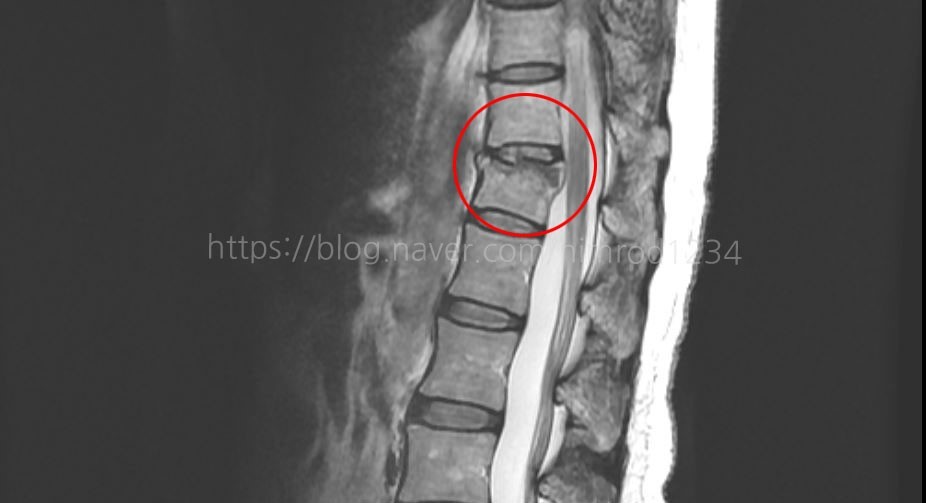

3. 진단

신체검사와 X-선 촬영, CT, MRI로 압박골절 유무와 정도를 확인할 수 있습니다.